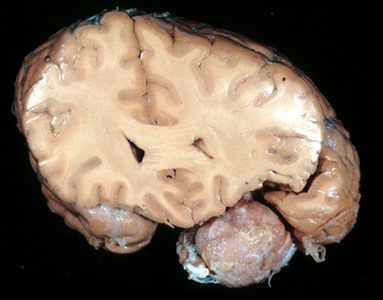

Question 20: Which of the statements about the lesion shown below is not true?

Incorrect. The image shows an extra-axial mass located, roughly, between the sphenoid ridge and the frontal lobe, consistent with a meningioma. Recurrence of meningioma is usually due to incomplete primary resection, not malignancy.

Correct. The image shows an extra-axial mass located, roughly, between the sphenoid ridge and the frontal lobe, consistent with a meningioma. Recurrence of meningioma is usually due to incomplete primary resection, not malignancy.